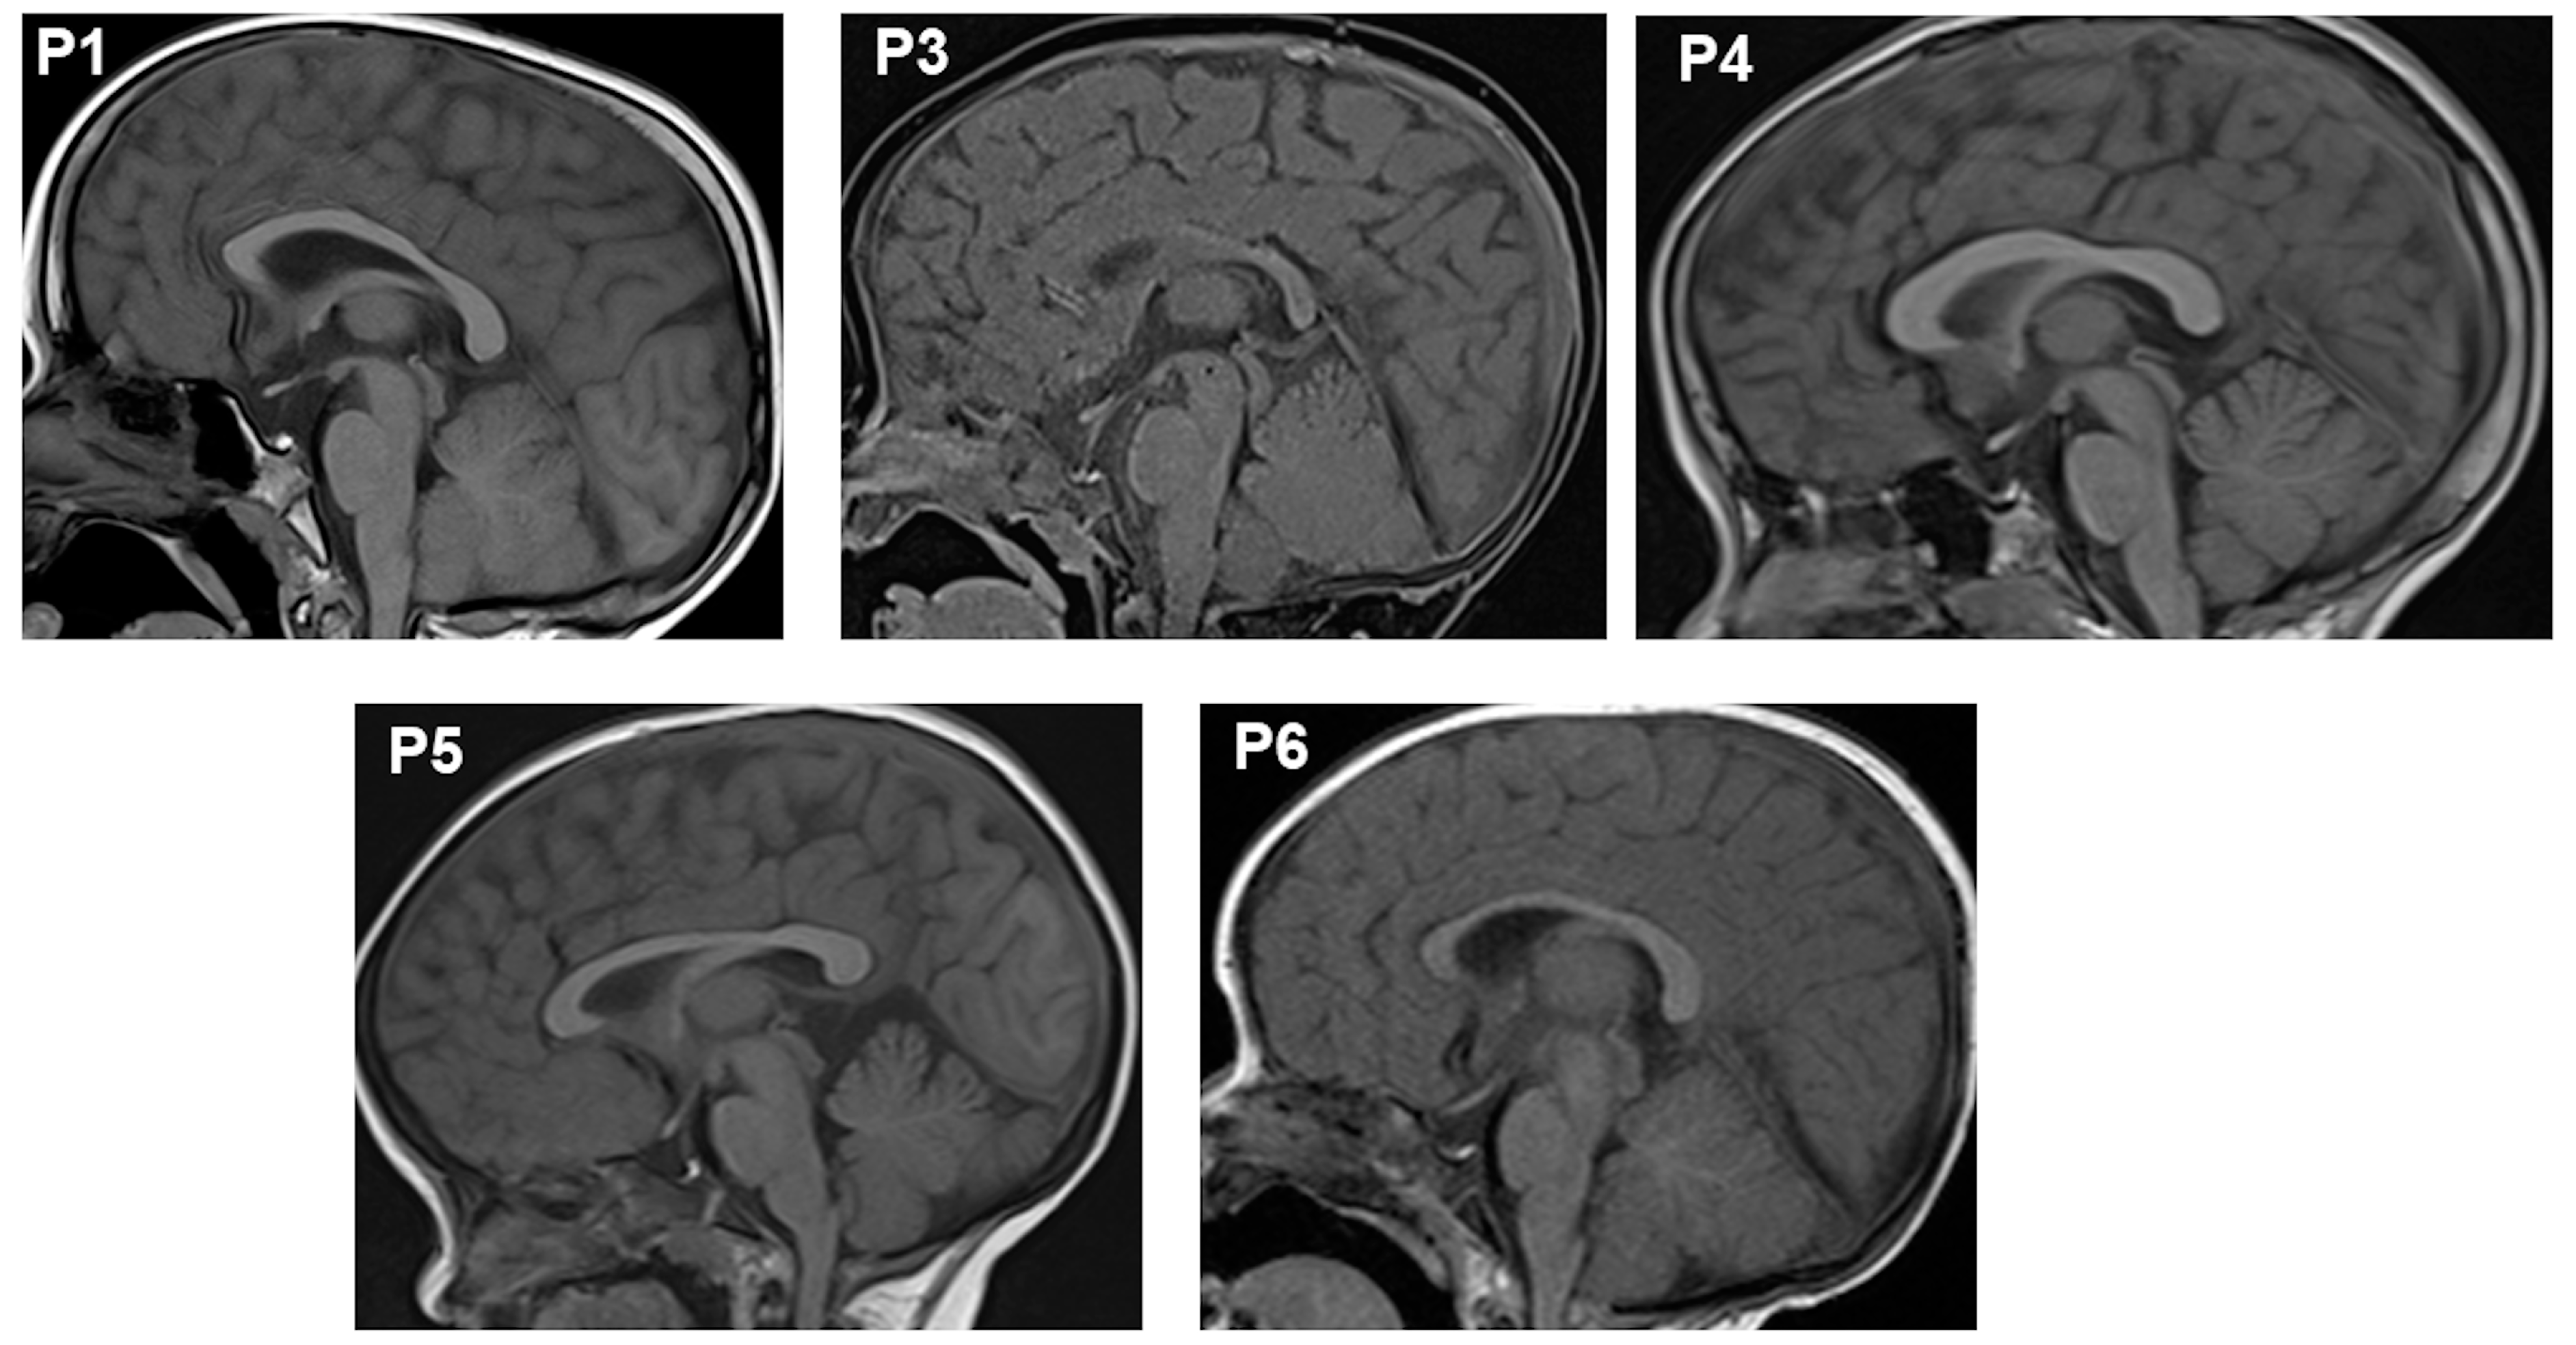

2.1. Clinical Findings

| Pituitary’s MRI | Anterior hypoplasia | Anterior hypoplasia | Anterior hypoplasia | Anterior hypoplasia | Anterior hypoplasia | Anterior hypoplasia |